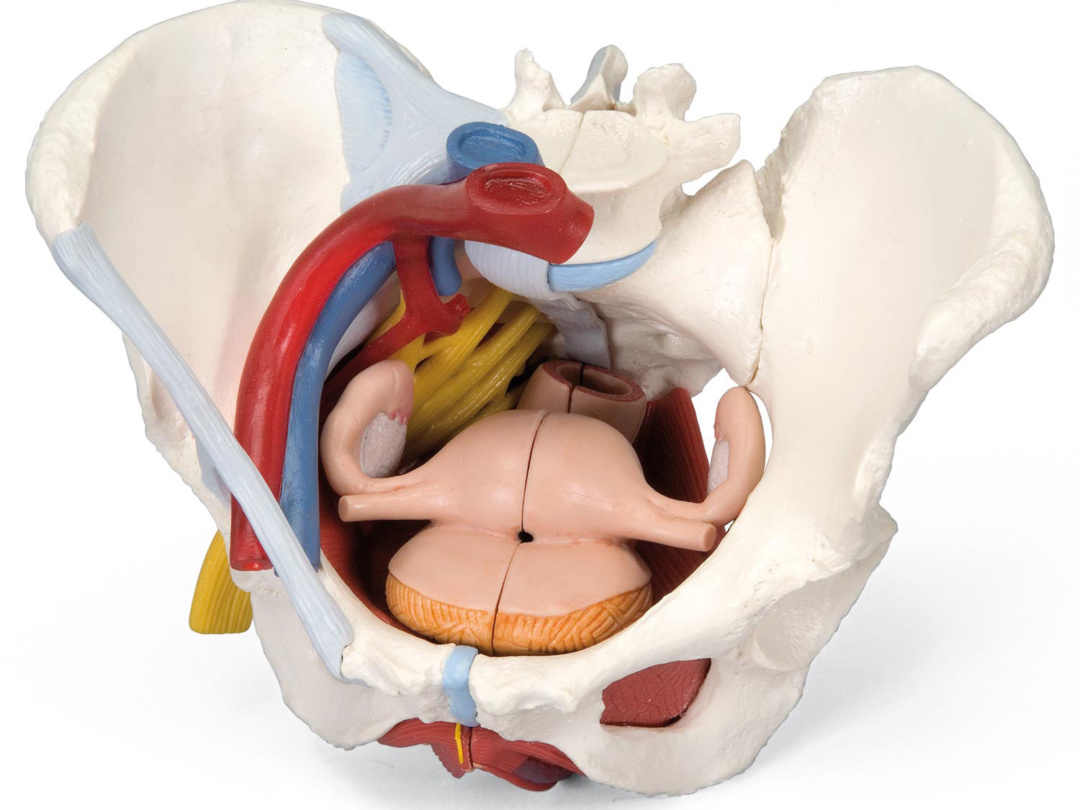

H10 女性骨盤内臓器 2分解モデル Medimann メディマン タカチホメディカル株式会社

女性骨盤内臓器 2分解モデル ボード型 日本スリービー サイエンティフィック

女性骨盤 内臓 骨盤底筋付 6分解モデル 日本スリービー サイエンティフィック

女性骨盤 内臓 骨盤底筋付 6分解モデル 日本スリービー サイエンティフィック